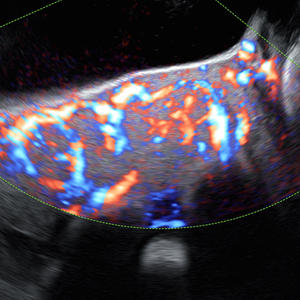

- Pionero en México en ofrecer diagnóstico por ultrasonido dentro del consultorio, así como en incorporar tecnología 3D y Doppler.